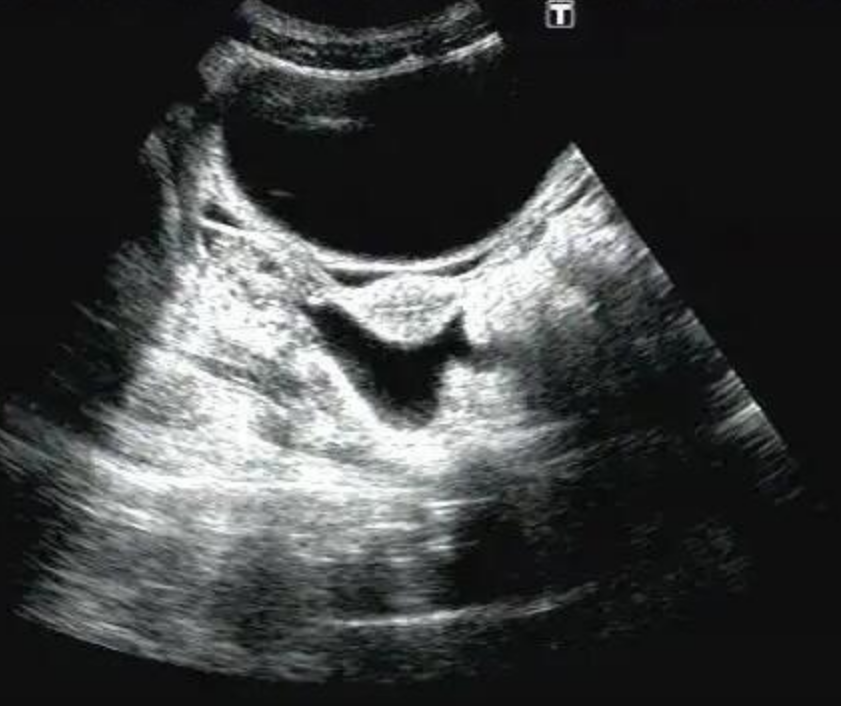

彩超检查盆腔积液,代表女性的盆腔内积聚了一定的液体。一般可分为生理性盆腔积液和病理性盆腔积液等。正常情况下女性盆腔的最低点是宫颈后方的道格拉斯腔,如果盆腔内存在一定的液体···...